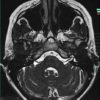

U dây VIII

» Thông tin: Nữ giới – 35 tuổi.

» Lâm sàng: Điếc đột ngột.